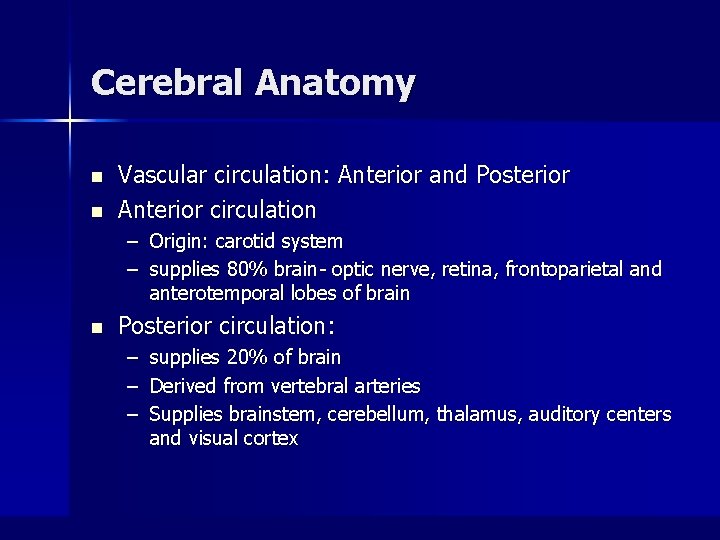

Cerebral Anatomy n n Vascular circulation: Anterior and Posterior Anterior circulation – Origin: carotid system – supplies 80% brain- optic nerve, retina, frontoparietal and anterotemporal lobes of brain n Posterior circulation: – – – supplies 20% of brain Derived from vertebral arteries Supplies brainstem, cerebellum, thalamus, auditory centers and visual cortex